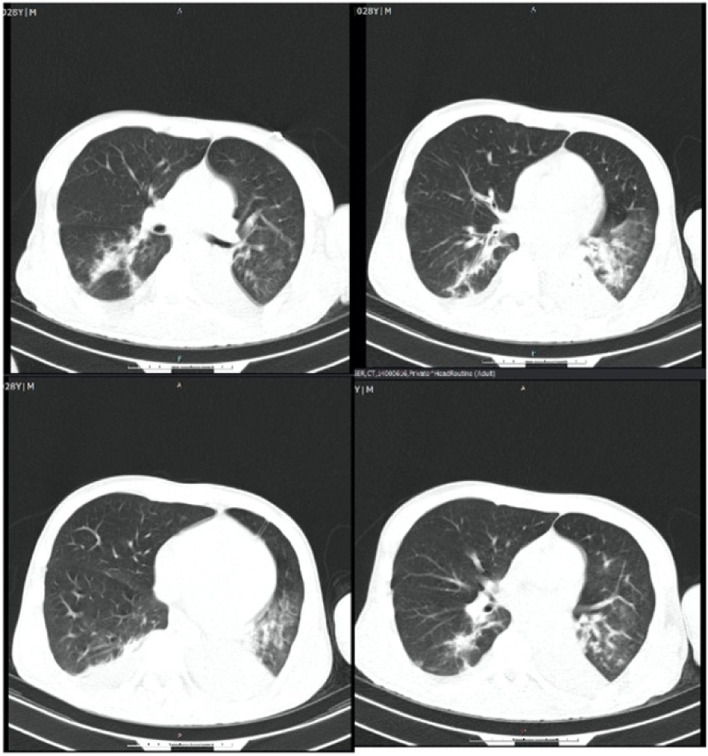

He was intubated and femoral catheterization was performed. Three vials of bicarbonate were intravenously administered. He underwent hemodialysis for eight hours but remained unresponsive. Serum/urine ketone and blood sugar were later returned to be positive and 411 mg/dL, respectively, indicating the possible presence of DKA. After initiation of insulin infusion, serum bicarbonate level started to rise. During admission, he had developed brain edema (Fig. 1). However, after appropriate treatment for DKA, the patient regained consciousness and was extubated. Since there were consolidations in his chest X-ray and lung computed tomography scan (Figs. 2 and 3), antibiotics and sepsis workup were ordered. He was initially treated by meropenem and vancomycin (for aspiration pneumonia); however, after consulting with the attending infectious disease specialist, he was started on levofloxacin. He was also receiving intravenous potassium, pantoprazole, heparin with prophylactic dose, and nebulized N-acetyl cysteine. Due to melena, endo-colonoscopy was performed but was reported to be normal. The other complication our patient experienced was deep venous thrombosis at the site of femoral catheter which mandated anticoagulation therapy with heparin drip. Diabetic ketoacidosis re-occurred twice more during the hospitalization. With the legitimate dose of methadone prescribed by psychiatrics, DKA completely resolved, and he was discharged home completely symptom-free after four weeks. Serial venous blood gas analysis, blood sugar and selected lab tests of the patient during hospital admission are shown in Figs. 4 and 5 and Table 2.

Fig. 3.

Lung computed tomography scan of the patient